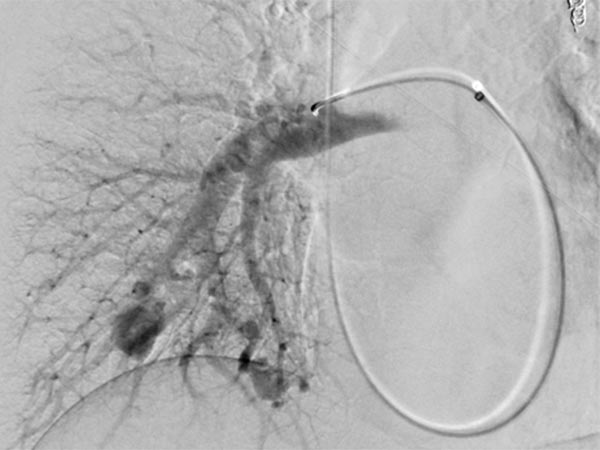

A guiding sheath was inserted into the right pulmonary artery from the neck (transjugular) via the heart, and a coaxial catheter was inserted through this by the Seldinger technique. After injection of contrast medium, pulmonary AVMs are also seen in the right lower lobe of the pulmonary circulation.

After cannulization of the larger pulmonary AVM, dilatation of the direct arteriovenous communication in the form of an aneurysm is seen. This is typical of Osler’s disease. The venous outflow is dilated, thus the risk of thromboembolism is particularly high.